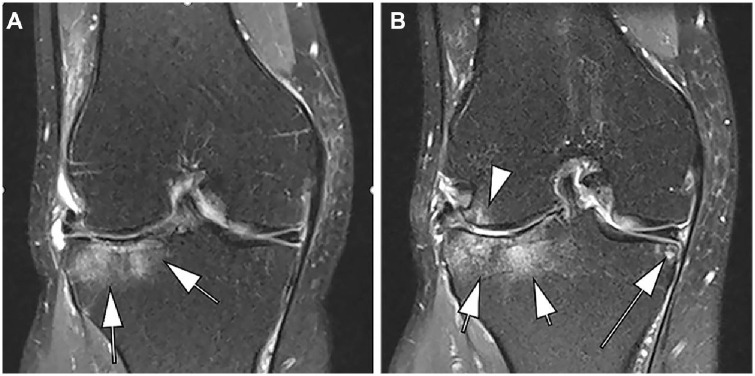

Abstract Image